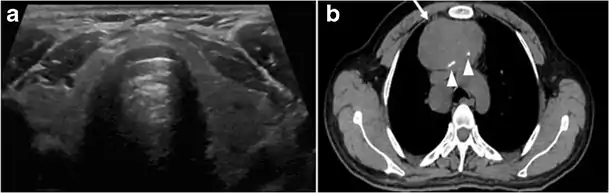

Goiter

A goiter is an abnormal thyroid gland proliferation that manifests as multi-nodular, uni-nodular, or non-nodular diffuse glandular enlargement. A goiter is formed of solid matrix, colloid cysts, blood products, calcification, and fibrosis, and this heterogeneity may lead to variable appearances on a CT scan (Figs. 13, 1414 and and15)15). The US is more sensitive in evaluating thyroid nodules within a goiter; however, a symptomatic goiter may require surgical treatment with total thyroidectomy, and in this case CT plays an additional role in preoperative evaluation. Specific aspects for examination on a CT scan during the preoperative evaluation for goiter include extension, mass effect, and suspicious features of malignancy.[1]

Malignancy can coexist within the goiter and a CT scan may give a clue if there are abnormal cervical lymph nodes and/or signs of invasion. Retrosternal extension (Fig. 15) could affect the surgical approach, as a lower extent may require a partial or total sternotomy to facilitate complete resection. Therefore, the distance of the retrosternal extent from the sternal notch should be measured on a sagittal image.[1]

The interpreting radiologist should describe the mass effect, detailing its degree and direction of displacement of central structures, including the trachea, oesophagus, larynx, and pharynx. Attention should be directed to the upper extent of the goiter and structures immediately surrounding the thyroid gland, including the neuro-vascular structures, retropharyngeal space, and pre-vertebral space. The reporting radiologist should evaluate the vocal cords for symmetry and signs of vocal cord palsy.[1]